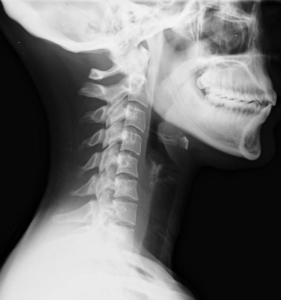

- Whiplash – Caused by the abrupt back-and-forth motion of the neck, whiplash can lead to severe pain, stiffness, headaches, and dizziness.

Though standard X-rays won’t diagnose soft tissue injury or head injury, other equipment will:

- MRI (Magnetic Resonance Imaging) – Detects soft tissue injury and head injury.